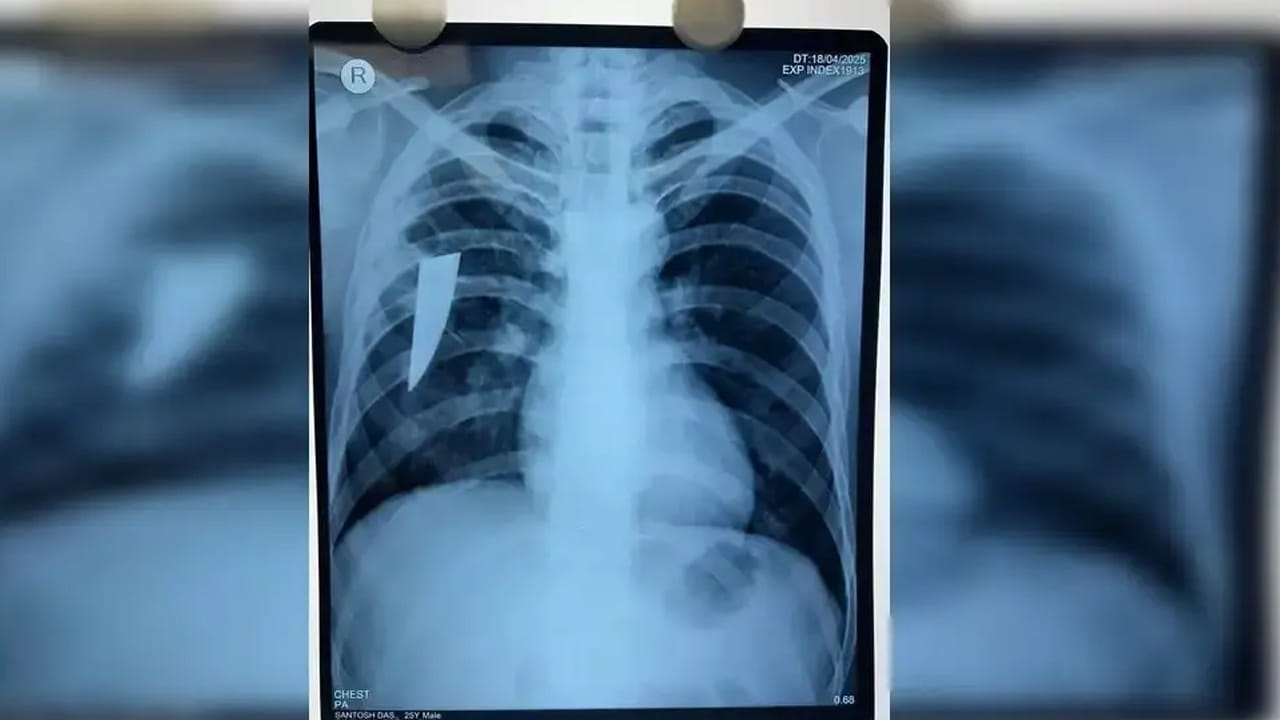

అది ఒడిశాలోని బెర్హంపూర్. అక్కడ గవర్నమెంట్ ఆధ్వర్యంలో నడిచే ఎంకేసీజీ మెడికల్ కాలేజ్ అండ్ హాస్పిటల్ ఉంది. 24 ఏళ్ల యువకుడికి దగ్గులో రక్తం పడుతూ ఉండటంతో.. ఏప్రిల్ 19న అతని కుటుంబ సభ్యులు అక్కడికి తీసుకుని వచ్చారు. దీంతో అతనికి పలు టెస్టులు చేశారు అక్కడి డాక్టర్లు. ఎక్స్ రే తీయగా అతని శరీరంలో ఏదో వస్తువు ఉన్నట్లు వెల్లడైంది. మరింత స్పష్టత కోసం.. CT స్కాన్, బ్రోంకోస్కోపీ చేయగా.. అతని కుడి ఊపిరితిత్తులో ఒక కత్తి ముక్క ఉన్నట్లు గుర్తించారు. వైద్యుల బృందం థొరాకోటమీ ఆపరేషన్ చేసి అతని ఊపిరితిత్తి నుంచి విజయవంతంగా ఎనిమిది సెంటీమీటర్ల పొడవున్న విరిగిన కత్తి ముక్కను తొలగించింది. ఆ కత్తి ముక్క వెడల్పు 2.5 సెం.మీ, మందం 3 మి.మీ ఉందని చెప్పారు. రోగి పరిస్థితి ప్రస్తుతం బాగానే ఉందని, ప్రస్తుతం ఆయన ఇంటెన్సివ్ కేర్ యూనిట్ (ఐసీయూ)లో పరిశీలనలో ఉన్నారని డాక్టర్లు తెలిపారు.

ఎంకేసీజీ మెడికల్ కాలేజ్ అండ్ హాస్పిటల్లోని CTVS, అనస్థీషియా విభాగాలలోని దాదాపు ఎనిమిది మంది వైద్యులు, నర్సింగ్ అధికారులు, పారా-మెడికల్ సిబ్బంది శస్త్రచికిత్స నిర్వహించి పదునైన లోహపు ముక్కను తొలగించారు. అయితే ఈ కత్తి ముక్క శరీరంలో అంత లోపలికి వెళ్లినప్పటికీ.. ఏ అవయవానికి డ్యామేజ్ జరగకపోవడం తమకు ఆశ్చర్యపరిచింది అని వైద్యులు చెప్పారు.(Source)